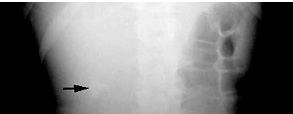

Renal stone

Presented with renal stone and hypercalcemia